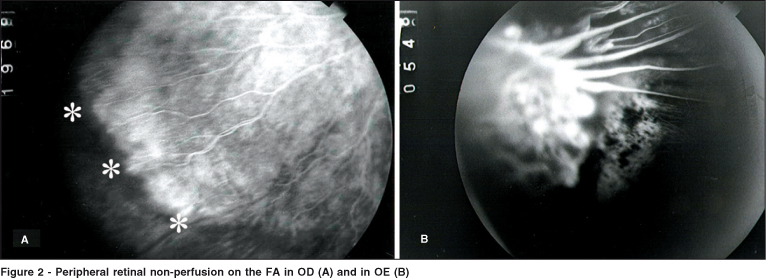

Her best correct visual acuity (BCVA) was 20/25 in OD and 1/200 in OS. The intraocular pressure (IOP) was 12 mmHg and biomicroscopy was normal in OU. The retina was attached in OD and temporal macular dragging could be seen bilaterally. There was tractional retinal detachment in OS involving the dystrophic macula temporally under thick epiretinal membranes (Figure 1). A broad linear macular fold due to posterior hyaloidal contracture was also present. Retinal vessels were straightened as they reached the equator and a fluorescent angiography (FA) disclosed important non-perfusion in the retinal periphery in OU (Figure 2).

We have described a young girl with osteoporosis, reduced bone mass and a retinal phenotype typical of FEVR, including avascularity of a large portion of the peripheral retina, reduced visual acuity, temporal dragging of the vessels emanating from the optic disc, epiretinal membranes and, eventually, tractional retinal detachment.